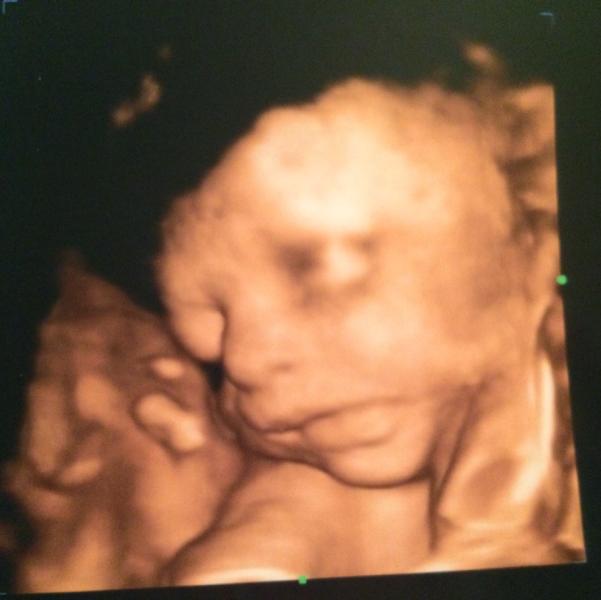

Девочки- красавицы! Делюсь информацией о прекрасной акции, специально для нас😍 сегодня (27.08) сходила на 3д с допплерометрией всего за 1800🎉 в "Медицентр" на Пионерской! Потрясающий врач В.В.Гиндрюк все подробно рассказал, целый час мы с мужем, который сидел в отдельной комнатке с большущим экраном, любовались нашим сыночком😍 все у нас в норме, идем день в день, только не любим фотографироваться! Руками и ногами наш мальчик прятал личико, но доктор таки исхитрился и у нас все таки есть снимок н...